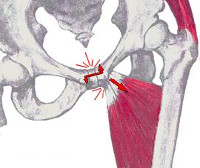

Анатомия и упражнения: Перекос таза и мышцы бедра